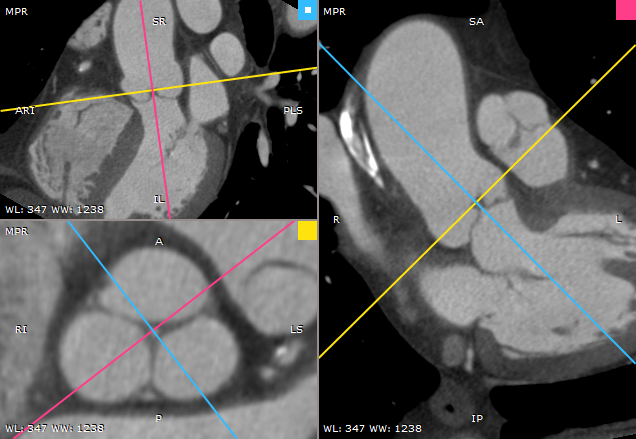

RadiAnt DICOM Viewer 内置的 3D MPR 工具可在任意平面(斜面)上重建图像,帮助实现仅凭基础图像无法实现的解剖结构可视化。